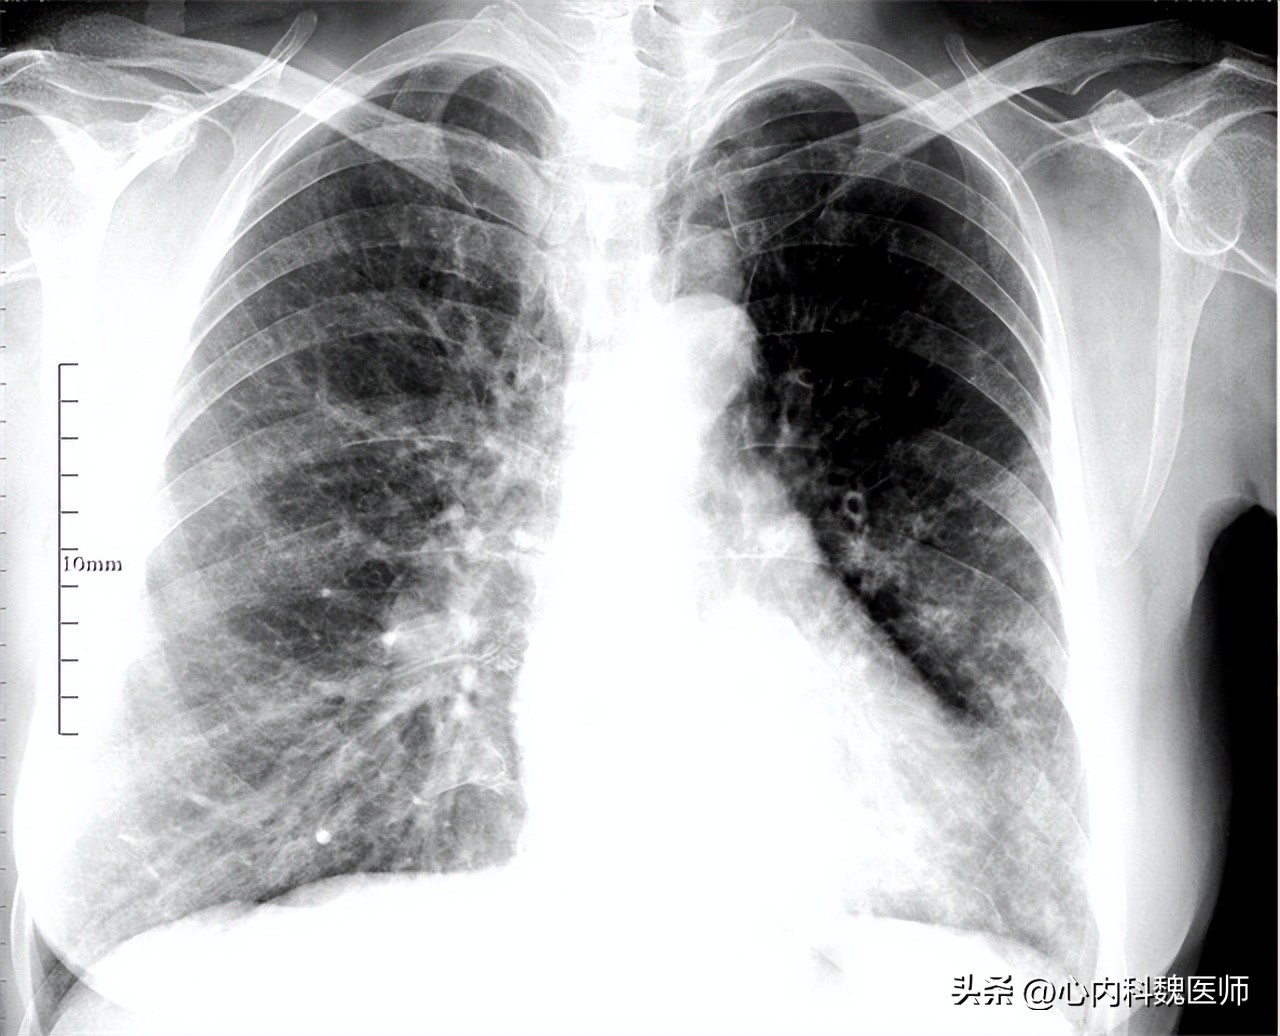

李先生挂了呼吸科,并与医生说明了这段时间表现的症状,医生猜测可能有肺部感染等问题,于是开了相关检查。血液检查结果显示白细胞计数、中性粒细胞计数都有所升高, X线检查提示肺纹理增粗、紊乱,并表现出条索状阴影,痰液检查可培养出肺炎链球菌, 根据李先生表现的症状及检查结果分析, 李先生是患上了慢性支气管炎 。